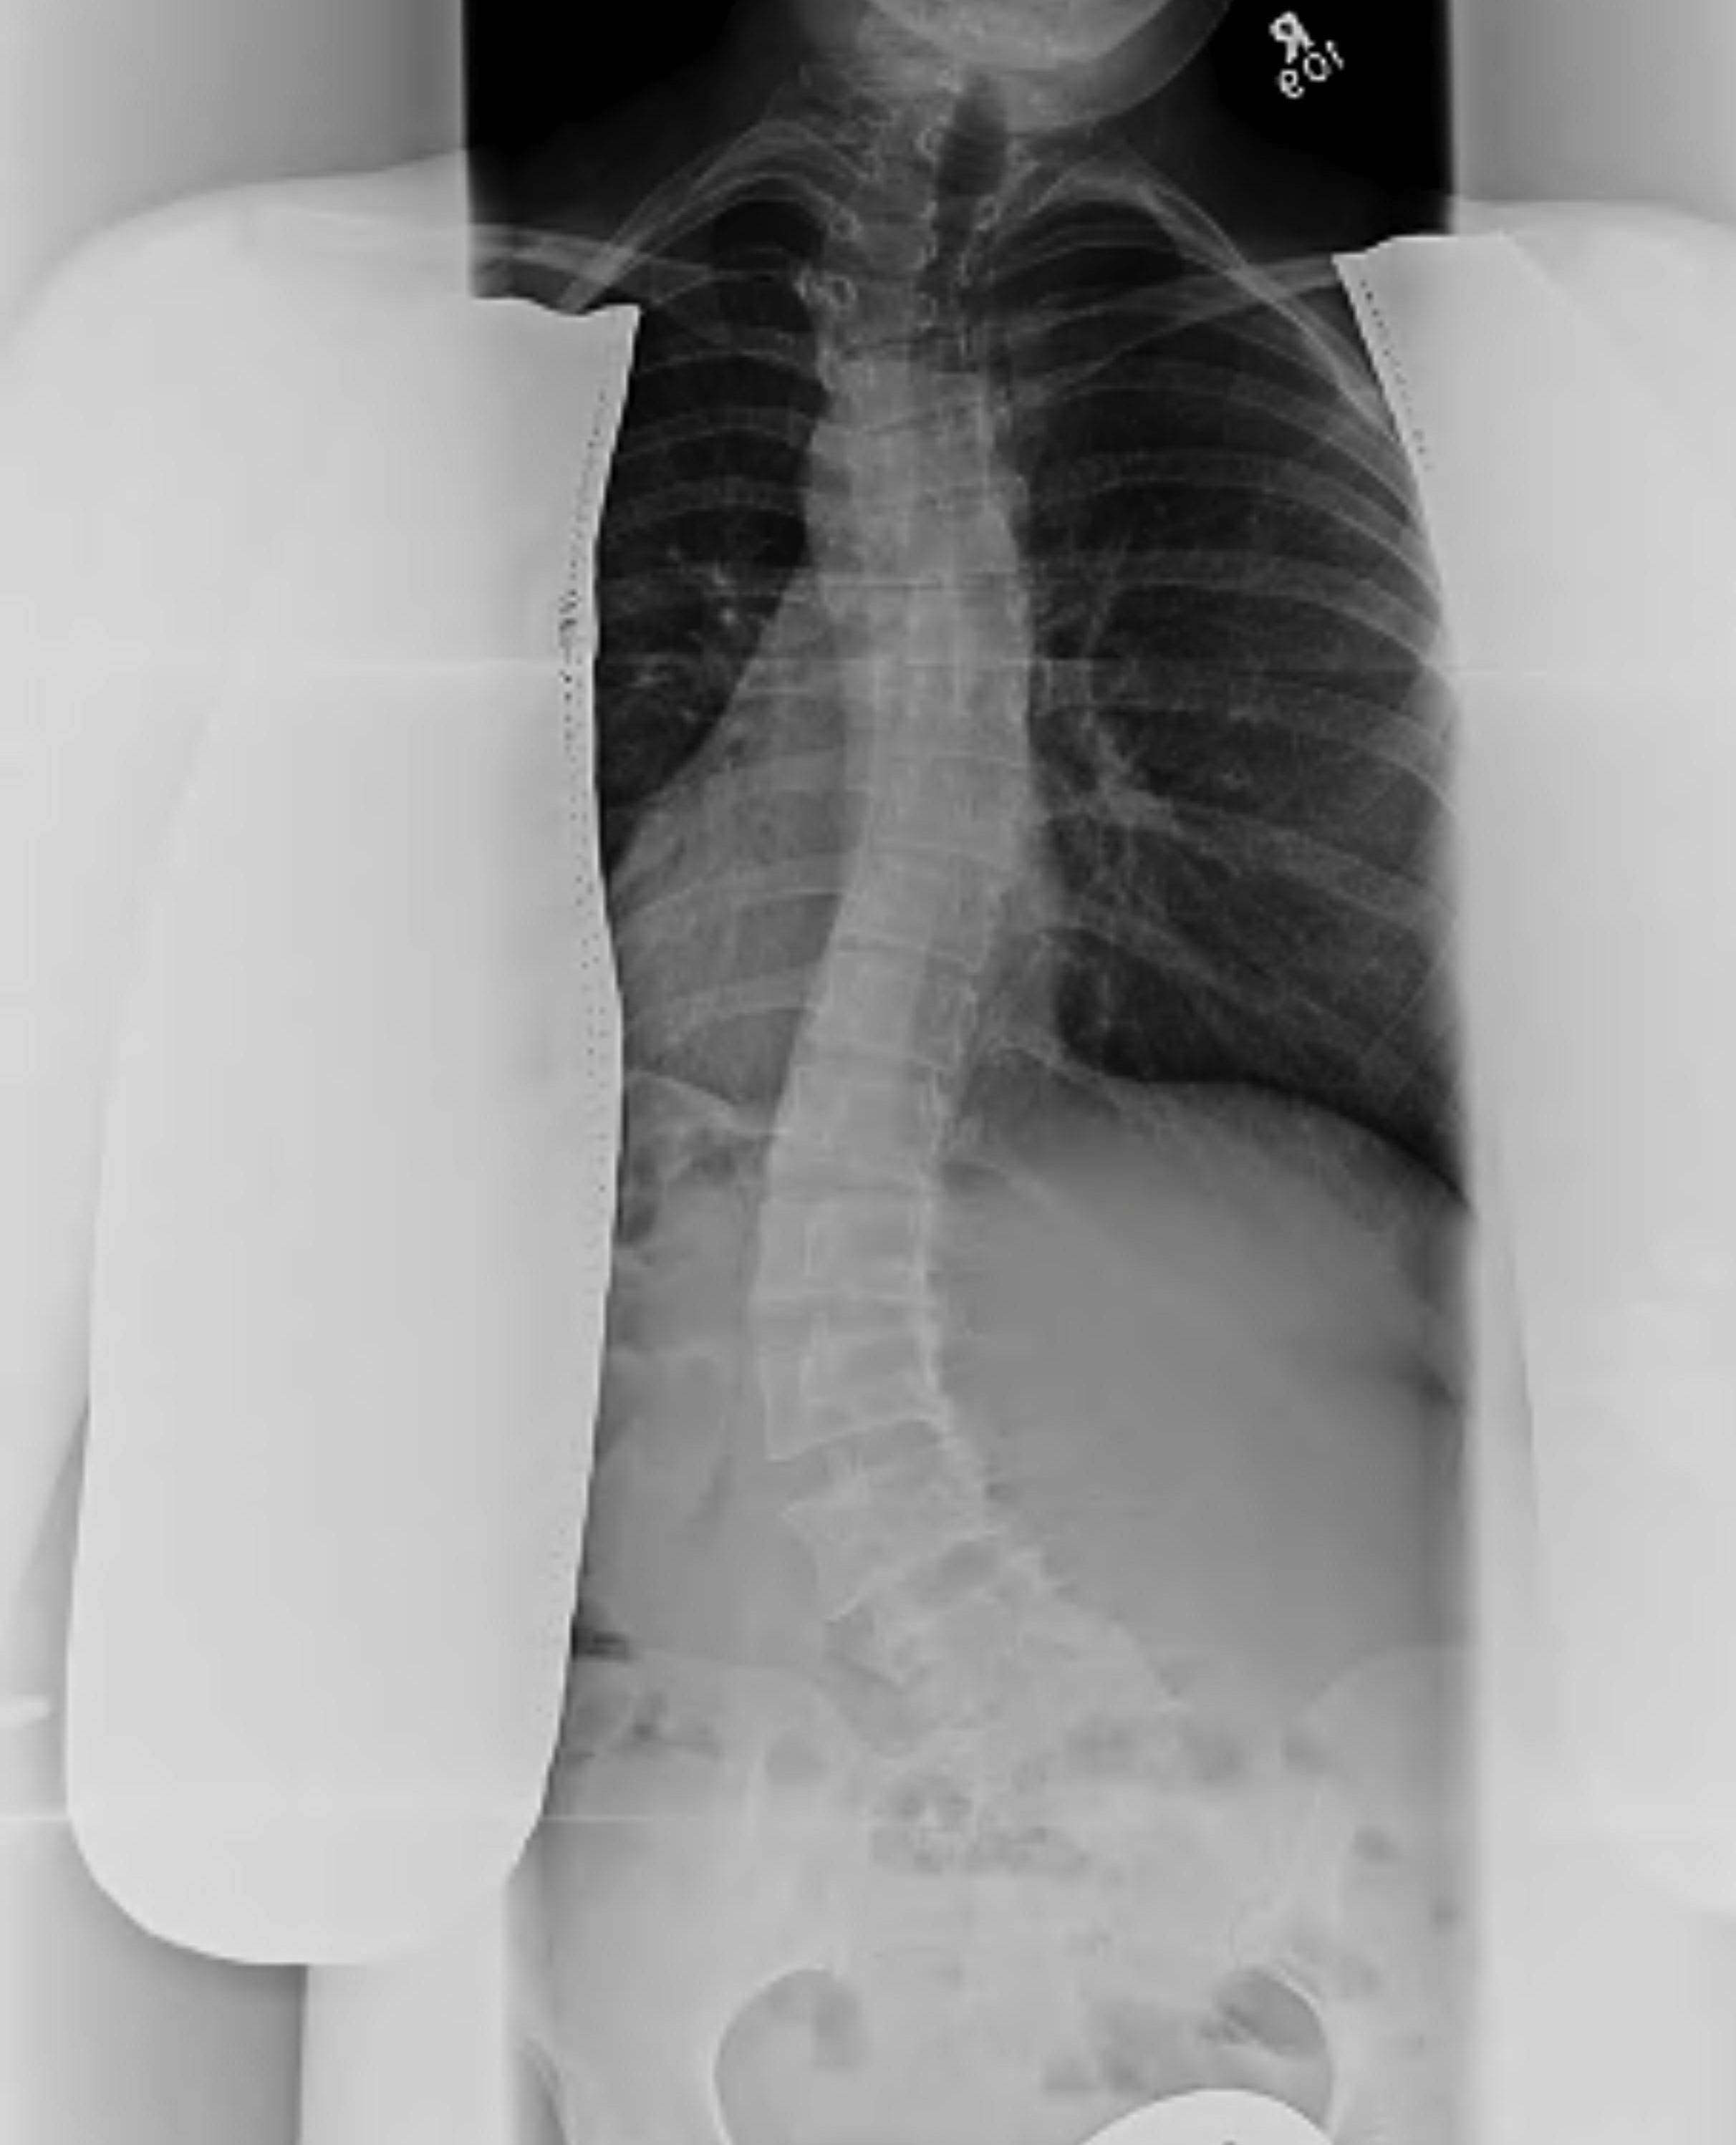

AP Film

Standing AP or PA films of whole spine including the iliac crests

- PA has less radiation to ovaries and breasts